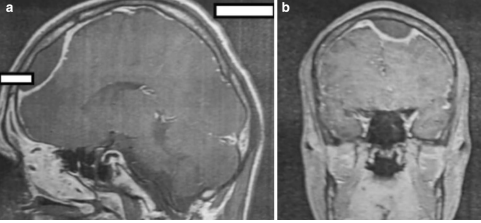

در یکی از بیماران، چندین آبسه مغزی در لوب فرونتال و جداری مشاهده شد (شکل ۴). سه بیمار با ترومبوز سینوس علامت دار (۰، ۲ و ۱ در دوره های مربوطه) در کلینیک بستری شدند. دو بیمار سربریت داشتند. پانزده بیمار مبتلا به مننژیت بودند: هشت نفر با سبب شناسی استافیلوکوک یا استرپتوکوک و یک نفر هم با سبب شناسی ویروسی تشخیص داده شده. در دو بیمار، مایع مغزی نخاعی استریل بود (جدول ۲ و ۳).